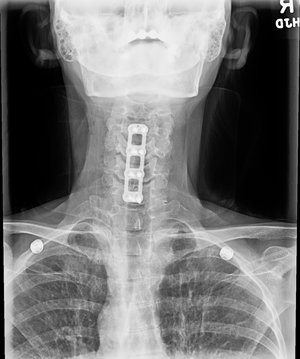

Posterior Cervical Laminectomy & Fusion